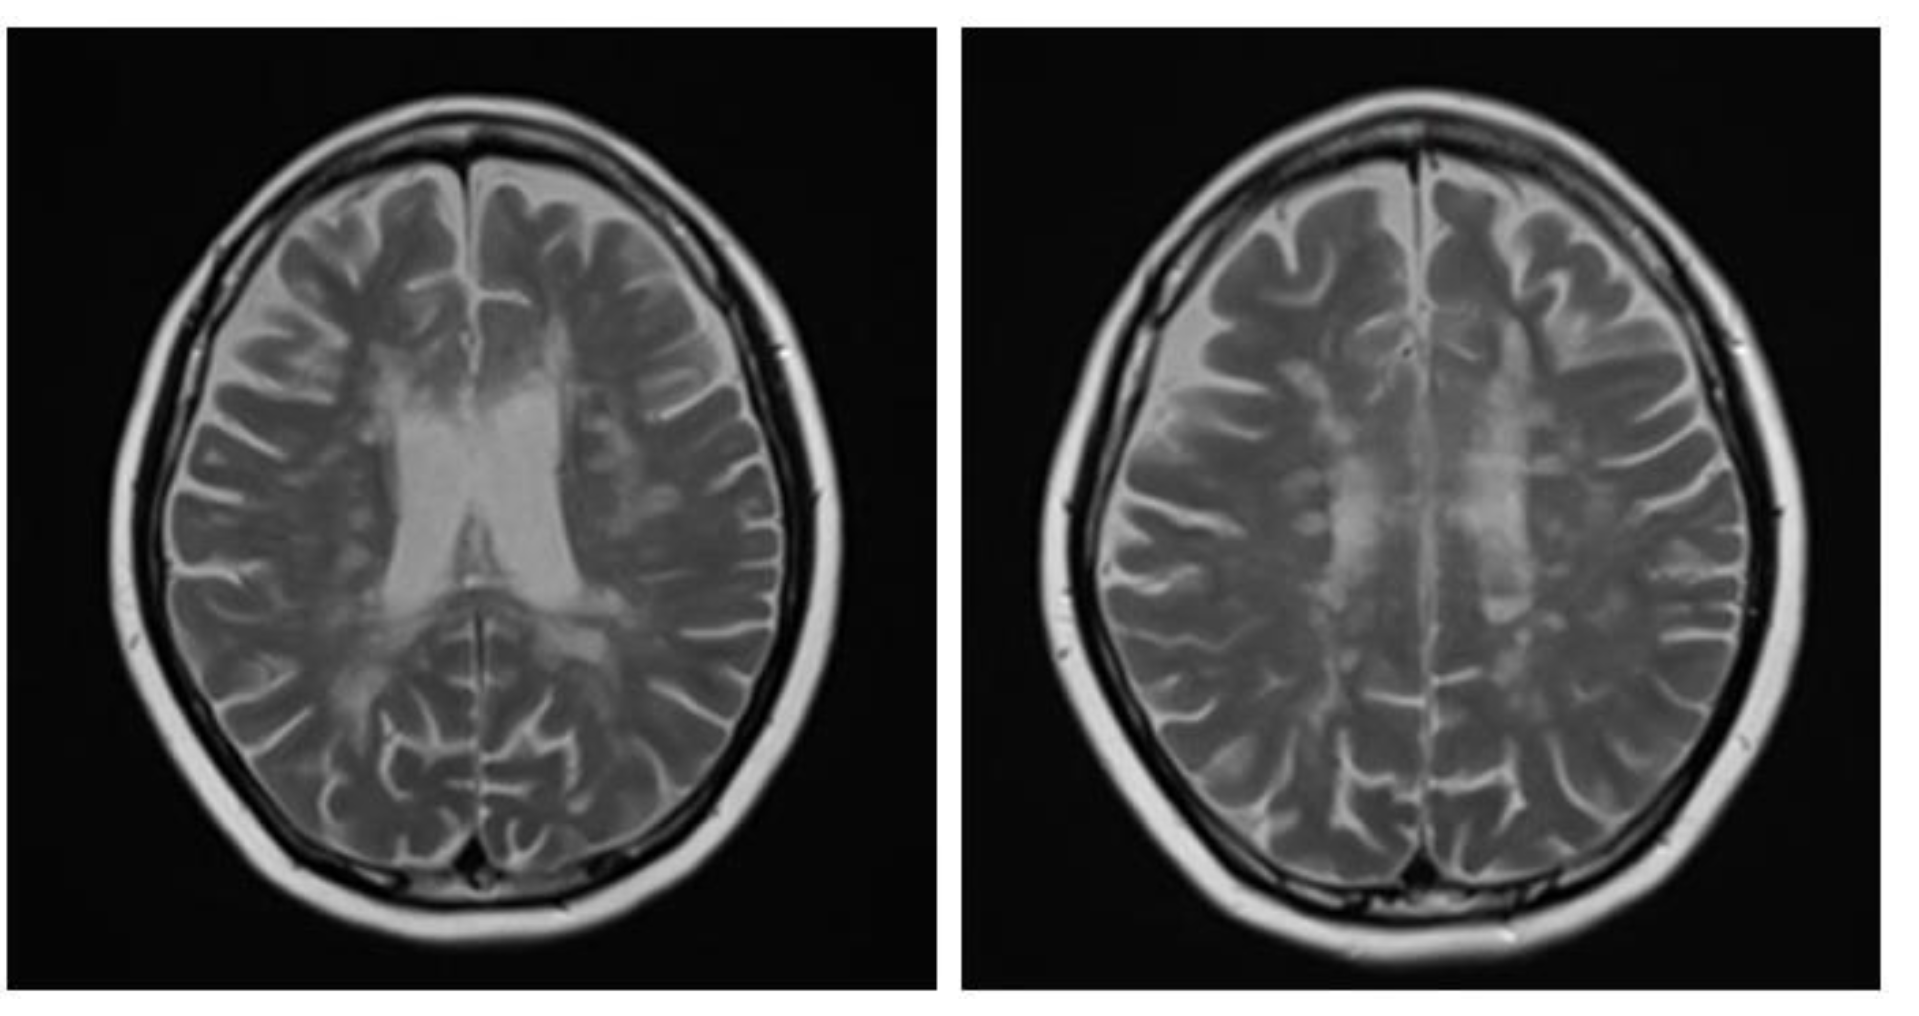

Figure 5. Axial T2W images of the same patient showing extensive hypersignal–intensity lesions scattered at juxtacortical region, subcortical region, deep white matter and periventricular white matter of bilateral cerebral hemispheres.

A brain MRI was available for all 32 patients, all of whom showed abnormalities. Most of the patients (19, 59.4%) were subjected to MRI soon after clinical presentation and during follow-up. The lesions were most commonly identified in the periventricular regions (78.1%), juxtacortical regions (75%) and deep white matter (62.5%). Cortical lesions were identified in only eight patients (25%). Other locations included in the McDonald criteria (2017) were the brainstem and cerebellum, which were found in 59.4 and 21.9% of all patients, respectively. The most common characteristic of the lesions was a round/oval discrete appearance (29 patients, 90.6%). A T1W-blackhole and classic Dawson’s finger (Figure 1) were equally identified in 20 patients (62.5%). A tumefactive form was found in two patients (Figure 2 and Figure 3). There were also two patients with target-like lesions, resembling Balo’s concentric sclerosis (Figure 4). The maximal diameter of the lesions was most commonly less than 13 mm (34.4%). A few patients showed lesions measuring more than 52 mm (9.4%), particularly those with confluent lesions. The total number of lesions in the T2W images was most commonly counted at less than 23 (50.0%), while there were up to four patients with extensive lesions, or more than 47 (12.5%) (Figure 5). Gadolinium-enhancing lesions were identified in nine patients (28.1%), who mostly only had one or two of these lesions (in five out of nine patients). Of these, the most common enhancing pattern was nodular enhancement (in four patients). The classic incomplete ring enhancement was identified in two patients, while complete ring enhancement was found in one patient. A visual assessment of the brain volume found brain atrophy in four patients (12.5%). Two patients with tumefactive MS showed brain swelling (Table 2).